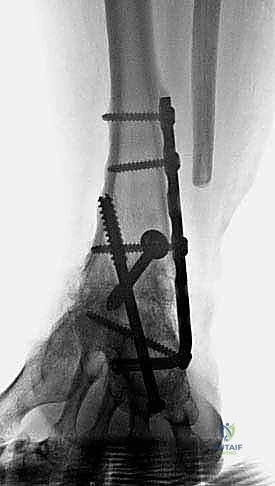

هنا تبرز الصفيحة النصلية (Blade Plate) كالحل الذهبي. تتميز هذه الصفيحة بوجود "نصل" صلب يتم إدخاله بقوة داخل عظمة الكعب، بينما يتم تثبيت الجزء الطولي من الصفيحة على عظمة قصبة الساق بالبراغي. هذا التصميم الهندسي يوفر مقاومة هائلة لقوى الانحناء والدوران، مما يضمن ثباتاً فورياً يسمح للعظام بالالتحام بشكل مثالي.

3. استئصال العظام التالفة (Talectomy)

في حالات "شاركو" المتقدمة، تكون عظمة الكاحل (Talus) مجرد فتات عظمي ميت (Avascular Necrosis). يتم استئصال هذه العظمة بالكامل، بالإضافة إلى إزالة أي غضاريف متبقية من أسفل قصبة الساق وأعلى عظمة الكعب لضمان تلامس عظمي حيوي ونظيف.

5. إدخال وتثبيت الصفيحة النصلية (Blade Plate)

هنا تكمن المهارة الجراحية الفائقة. يتم تشكيل مجرى دقيق داخل عظمة الكعب باستخدام إزميل خاص، ثم يتم طرق "نصل" الصفيحة المعدنية بحذر شديد داخل عظمة الكعب لضمان أقصى درجات الثبات.

6. التثبيت النهائي بالبراغي (Screw Fixation)

بعد التأكد من الموضع المثالي للصفيحة والنصل، يتم تثبيت الجزء العلوي من الصفيحة على عظمة قصبة الساق باستخدام براغي قشرية (Cortical Screws) قوية. يتم وضع العظام تحت ضغط ميكانيكي (Compression) لتحفيز الخلايا العظمية على الالتحام السريع.

7. الترقيع العظمي (Bone Grafting) وإغلاق الجرح